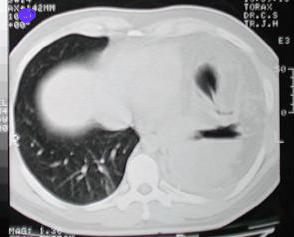

Tomografía Computarizada Tórax

Tomografía de ½ inferior del tórax y abdomen superior con contraste oral, se aprecia desplazamiento del fundus gastrico hacia la base pulmonar izquierda, la grasa epiploica, la brecha diafragmatica, tambien el proyectil y esquirlas metalicas.